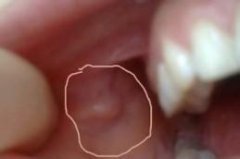

石家庄九州皮肤病医院 > 尖锐湿疣 > > > 尖锐湿疣患者家庭应当怎么避免传染呢?尖锐湿疣临床上主要是在患者的生殖部位出现病毒感染,在发病的时候虽然症状比较突出,但是却没有什么痒痛伤害,可是对于尖锐湿疣患者还是应当不要忽视的,应当尽早的发现尽快的去治愈,对于尖锐湿疣越早的治愈受到的伤害也就越小,所以建议患者最好还是能够去正规的治疗,当然在治疗上患者应当注意正确的选择药物方法,要注意能够标本兼治才能彻底的治愈。

尖锐湿疣患者家庭应当怎么避免传染呢?尖锐湿疣是可以对患者造成很大的生殖健康损害,而且尖锐湿疣也是可以导致患者生活质量受到影响的,所以尖锐湿疣越早的治愈越好,而目前临床上治疗尖锐湿疣是有很多药物方法的,但是患者的治疗未必能够有效的得到治愈,大多数患者虽然治疗有一些物理方法是可以帮助患者快速消除尖锐湿疣的症状,但是物理治疗未必能够消除尖锐湿疣的病毒,所以建议患者要慎重的选择方法才好。